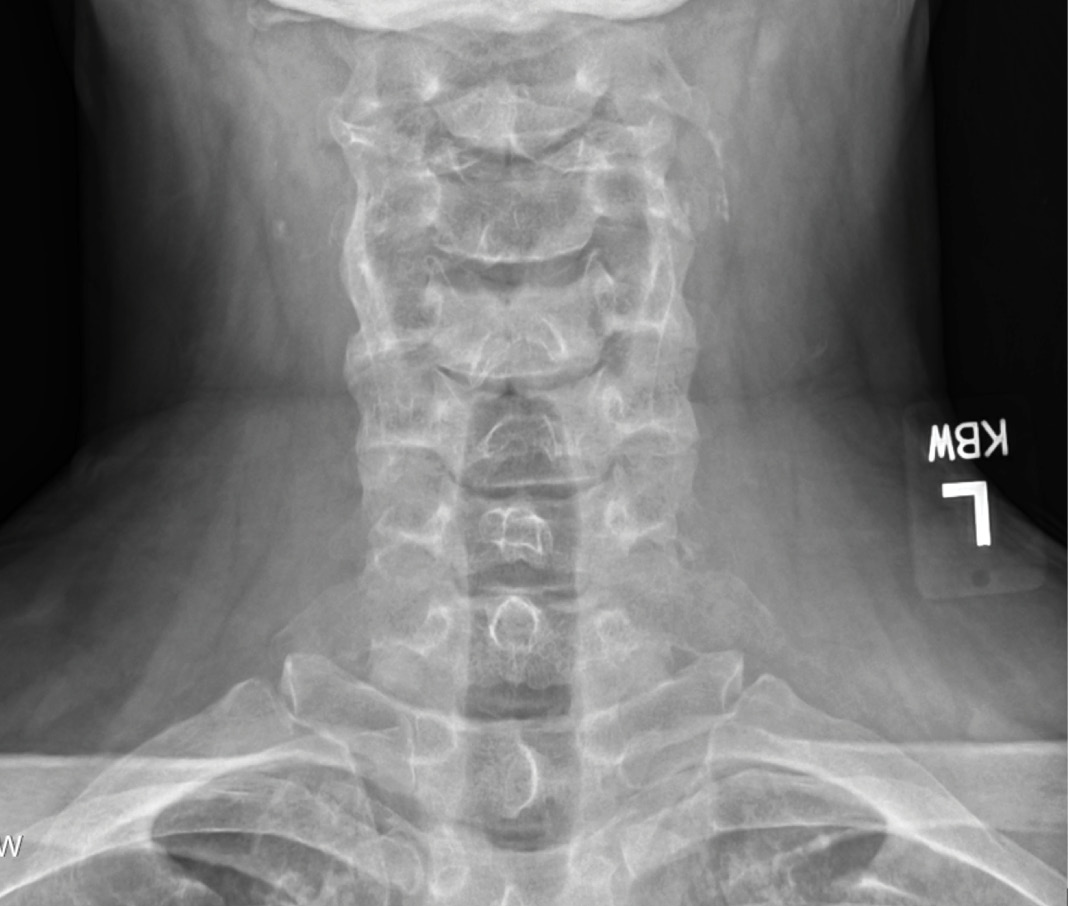

MRIs illustrated mild degenerative disc disease from C4-6 with disc herniations at both C4-5 and C5-6. The axial slice through C4-5 showed a right central disc herniation causing central and mainly right-sided foraminal stenosis. The axial slice through C5-6 showed a central disc herniation also causing central and mainly right-sided foraminal stenosis. The axial slice through C6-7 showed a left-sided disc herniation causing some left-sided foraminal stenosis, however, the patient did not demonstrate any left-sided symptoms.

Upon examination, the patient had good motion on flexion-extension, so fusion was not considered at all. My operative plan was to use prodisc cervical devices and replace both discs at C4-5 and C5-6, giving me the flexibility to use either a domed or flat implant.

During the procedure, prodisc C Vivo fit well within the C4-5 concave endplate. I expected to use a flat endplate prodisc C SK at C5-6, however I trialed the domed prodisc C Vivo and it actually looked good, so I unexpectedly used matching implants.